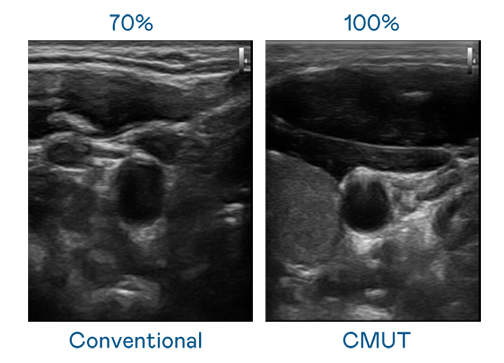

CMUT 技术是一种用电容式微机电元件来产生超音波讯号的技术。与传统 PZT 压电式技术相比,CMUT 频宽增加 30%,更宽频的超音波讯号让影像解析度大幅提升,是实现高影像品质医疗超音波扫描、促进精准医疗发展的关键技术。

大频宽带来超清晰影像

超音波影像的解析度高低,首先取决于探头能发出的讯号频宽。小蝌蚪视频免费观看视频 CMUT 可提供高清晰的超音波讯号,提供高频宽、高灵敏度、影像纹理细节更高的超音波影像,协助医护人员缩短影像判读时间及利用精准的医疗影像进行诊断。